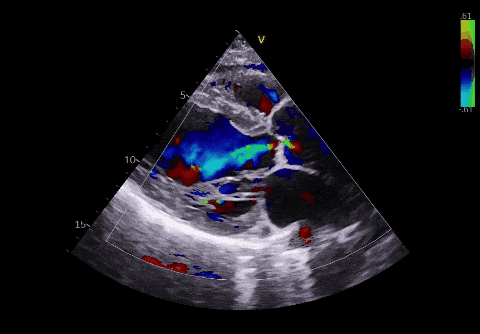

▲术前超声

左心室射血分数 (LVEF):这是衡量心脏“泵血功能”的核心指标。正常人的数值通常在 50%-70%。